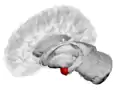

Dorsal view of the amygdala in an average human brain

Left lateral view of the amygdala in an average human brain